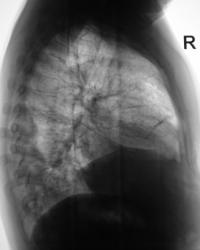

Пациент был направлен в рентгеновский кабинет терапевтом с диагнозом "Правостороняя пневмония". Было произведено стандартное исследование.

Было назначено противовоспалительное лечение. Через 1 неделю проведен "рентген-контроль".

Еще через неделю, также произведен "рентген-контроль".

Сегодня произвели "очередной контроль". Произвели рентгенографию в прямой и правой боковой проекциях. Решили также произвести томографию в правой боковой проекции.

правостороннего плеврального выпота в проекции средней доли.

Согласен с коллегой, но по-моему, кроме это выпот есть и заднем синусе. Картина в серия снимков №7-9, с небольшой положительной динамикой в сравнении данными в серии №4-6.

Кажущееся затемнение в области средней доли симулирует суперпозиция приподнятого правого купола диафрагмы и тени сердца. В заднем синусе справа - небольшой выпот, а со стороны диафрагмы, кроме элевации и выпрямления, присутствует картина диафрагматита в задних отделах. Вероятно необходимо ультразвуковое исследование органов брюшной полости и забрюшинного пространства для поиска первопричины данного состояния там. Динамика процесса за время наблюдения - явно положительная.